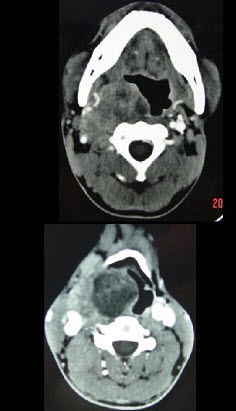

男,41岁,右侧咽部不适两年余,有异物感,声音嘶哑,CT如图所示,最可能诊断为()。

A、颈动脉体瘤

B、咽旁转移癌

C、咽旁淋巴瘤

D、小唾液腺瘤

E、咽旁神经鞘膜瘤

E